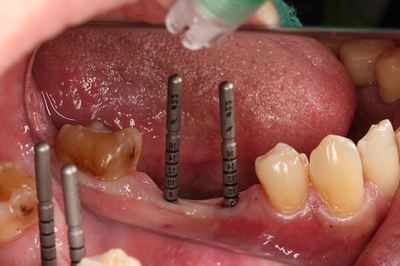

左下第二小臼歯・第一大臼歯の部分にインプラントを埋入します。(ミラー像)

サージカルステントをセットし安全な領域までドリリングします。

イニシャルドリルでのドリリングを終えました。

この段階でレントゲンを撮影して確認します。

確認を終えましたら遠心側のドリリングも進めます。

粘膜剥離前に安全な範囲で、ある程度のドリリングを終えました。